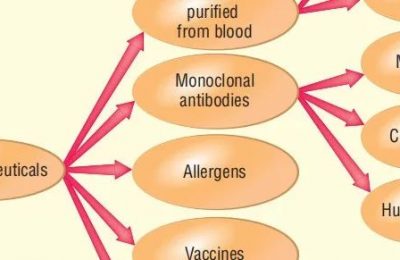

抗体或抗原的诊断试验

几种常规使用的诊断试验是基于抗体的特异性和高亲和力。本章的其余部分提供了如何进行不同测试的示例,并描述了每种测试的一般原则:这些检测既有定性,也有定量,有助于确定抗原或抗体的存在。